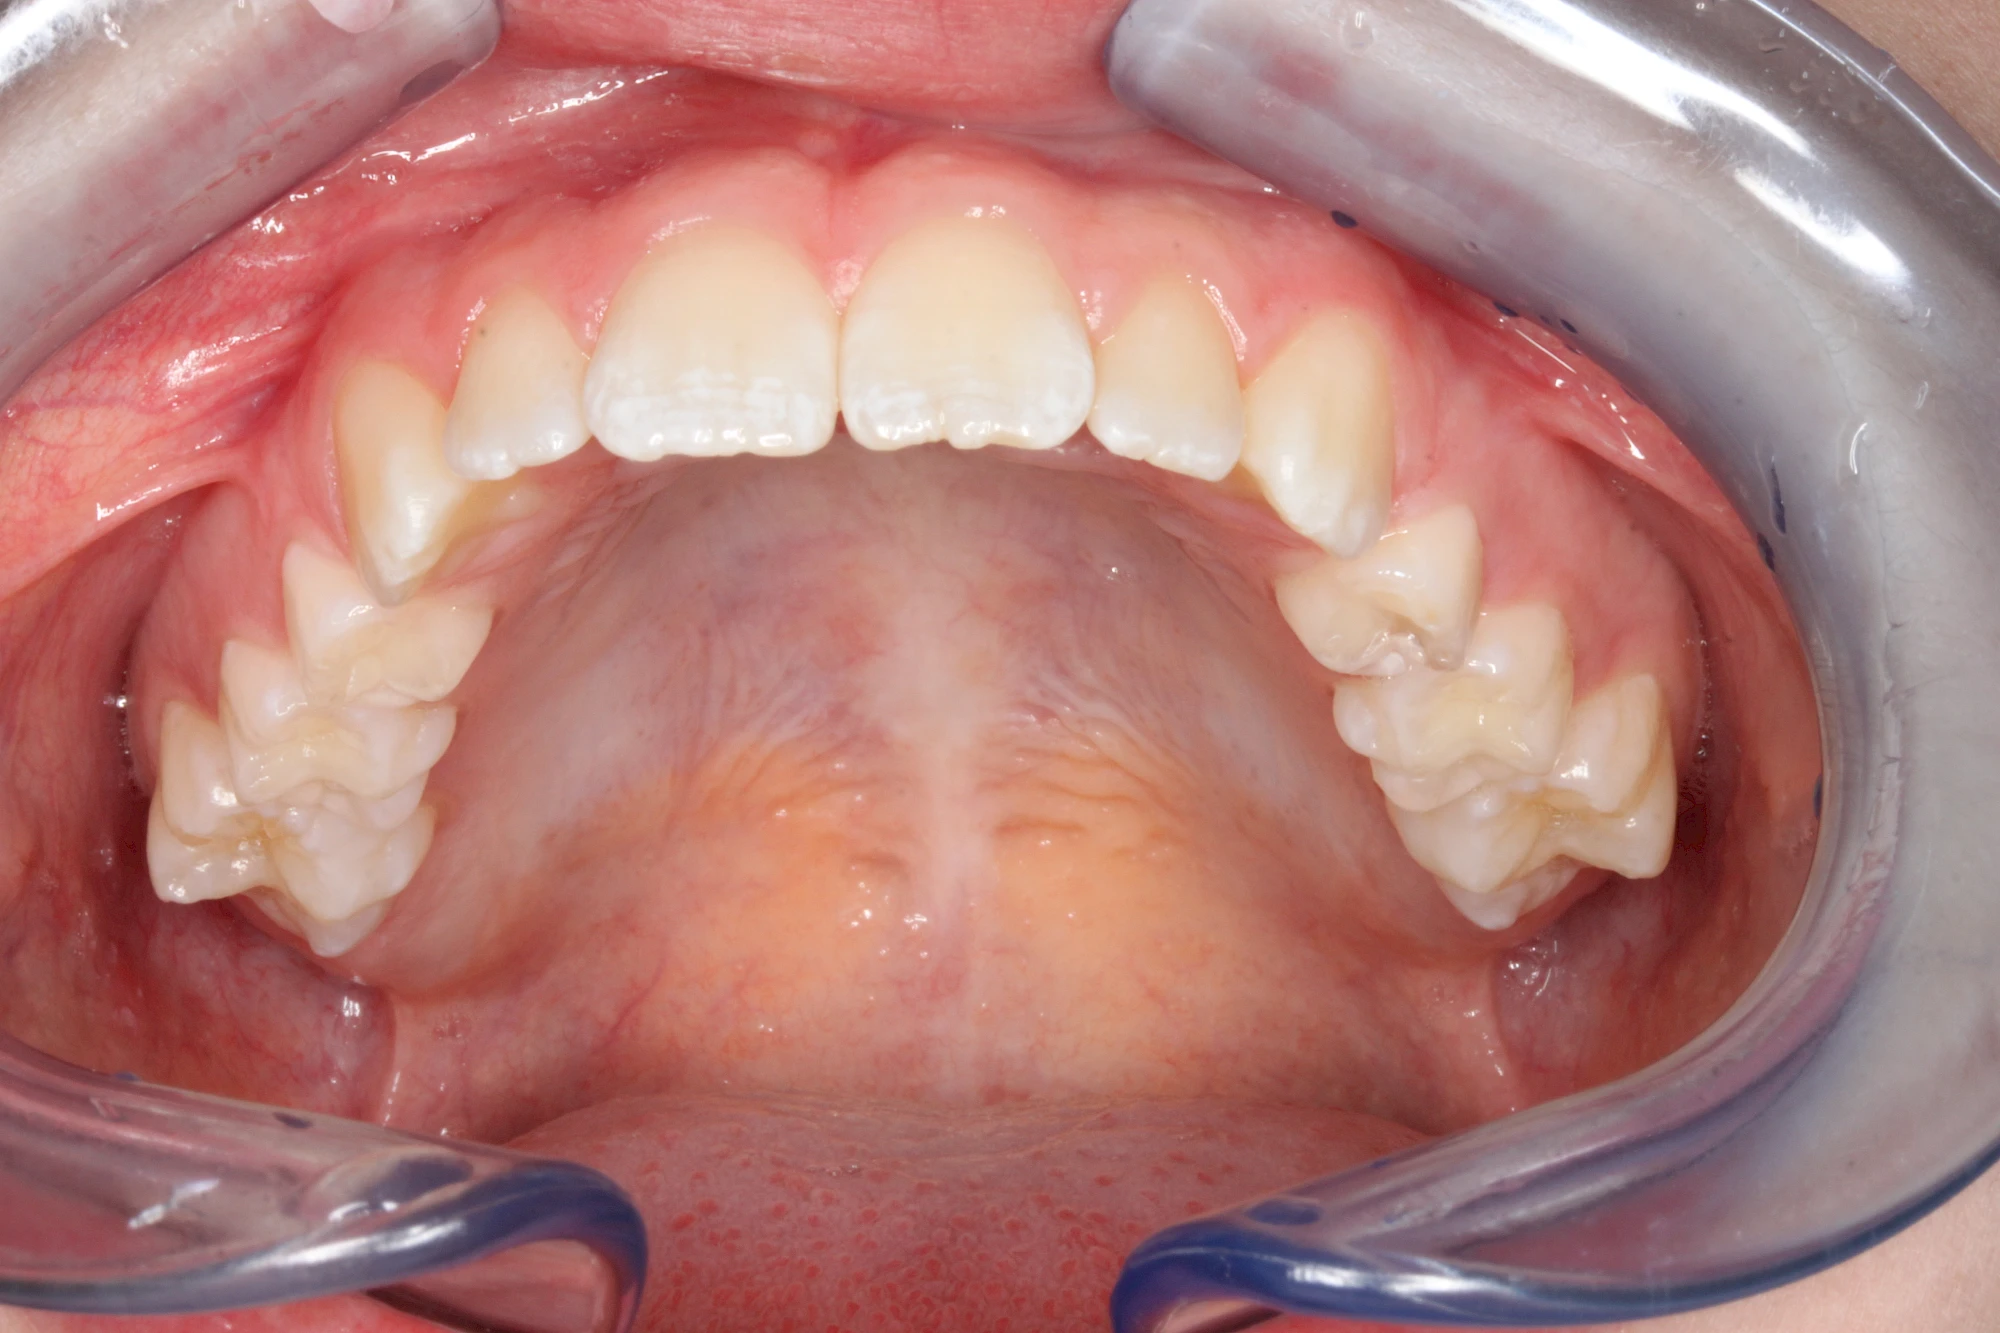

Gerade bei Kindern und Jugendlichen werden zunehmend häufiger bräunliche Verfärbungen mitunter auch mit Formveränderungen (die Oberfläche ist rauh oder zerklüftet) der Zähne beobachtet. Meist sind Schneidezähne oder Backenzähne betroffen. Dies könnte ein Hinweis auf sogenannte Kreidezähne (MIH: Molaren-Inzisiven-Hypomineralisation) sein.

Bräunliche Verfärbung